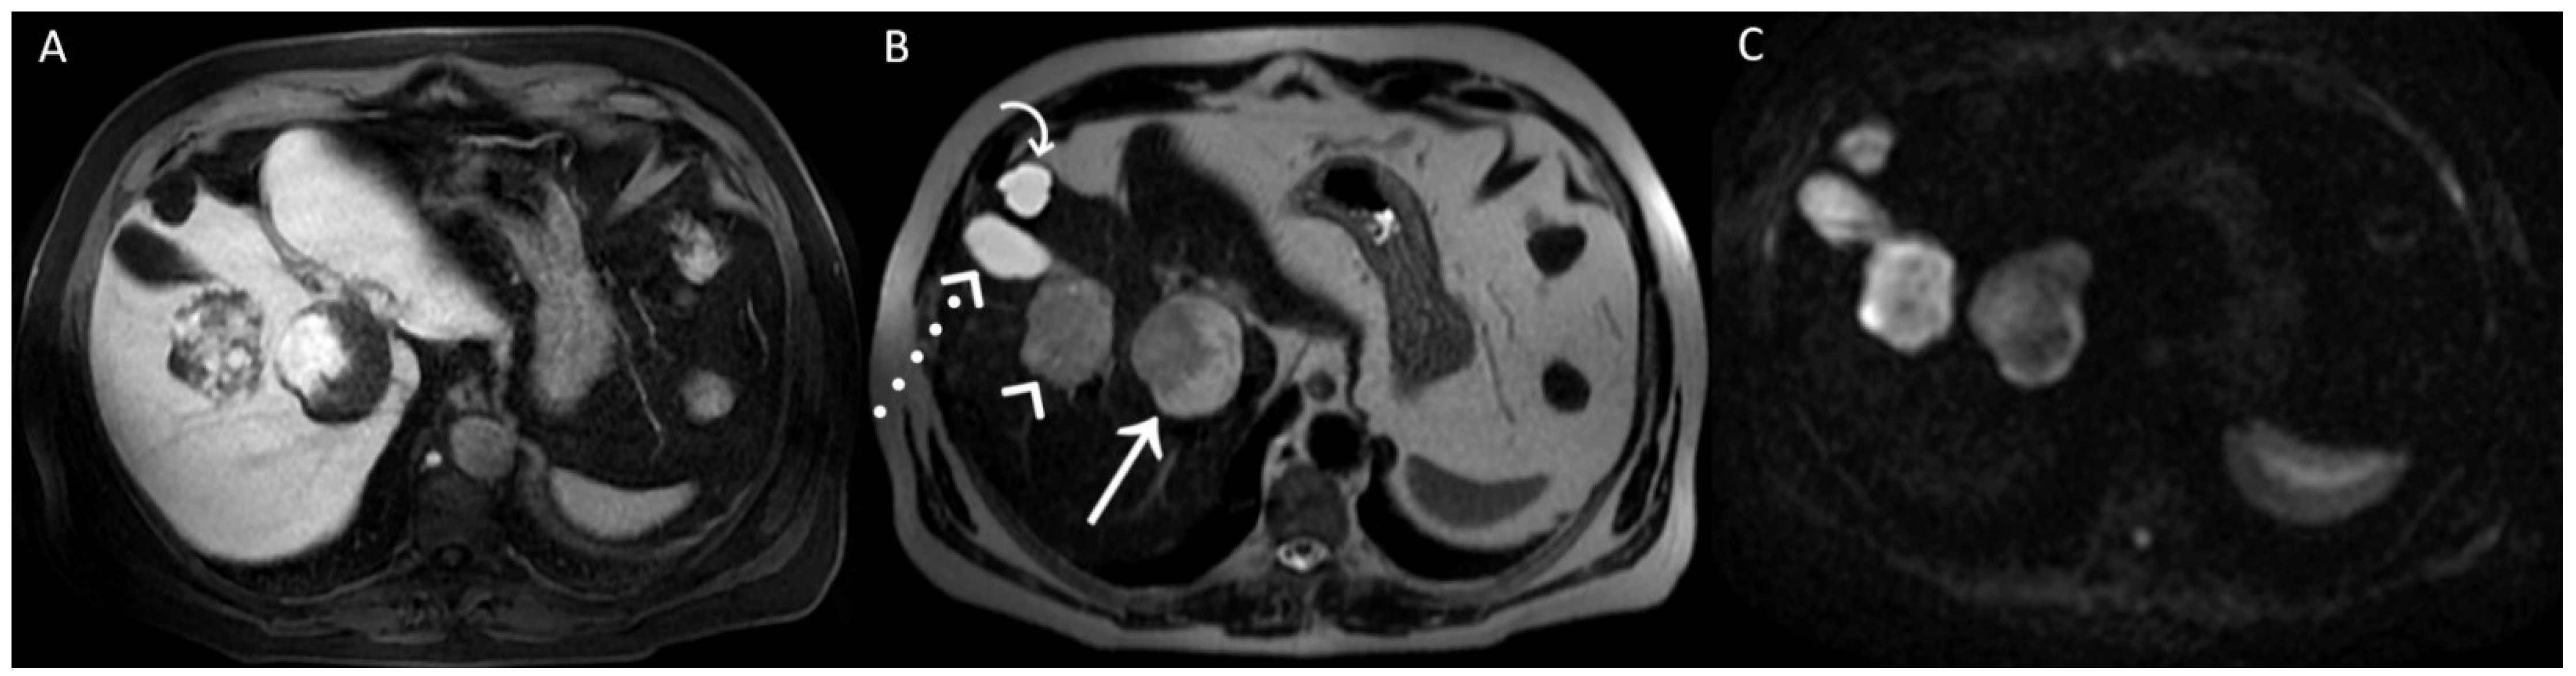

A posteriori, a perfect correspondence between the contrast agent globular enhancement on Axial T1-weighted fat saturated images in delayed phase (A) and the relatively hypointense areas on post-contrast T2WI (B) and DWI (C) was evident. Furthermore, the largest and deepest lesion showed a relatively hypointense area on DWI, larger than that on T2WI, due to later acquisition of DWI and progressive centripetal contrast filling of the lesion. On T2WI (B), we can also appreciate the comparison between the signal hyperintensity of different structures: cavernous hemangiomas (arrow and arrowhead); simple cyst (curved arrow), and gallbladder’s fundus (dotted arrow). T2WI and DWI are usually acquired after the acquisition of vascular phases in the dead time until the acquisition of the hepatobiliary phase to shorten the time-consuming protocols since it was demonstrated that T2WI and DWI acquired after Gd-EOB-DTPA showed a comparable diagnostic capability to pre-contrast T2WI and DWI in the detection and characterization of hepatic tumors [1,2]. In conclusion, when liver lesions of unknown nature must be characterized, with a lack of previous radiological investigations, it could be useful to acquire pre-contrast T2WI and DWI to avoid diagnostic confusion, especially in non-tertiary centers.